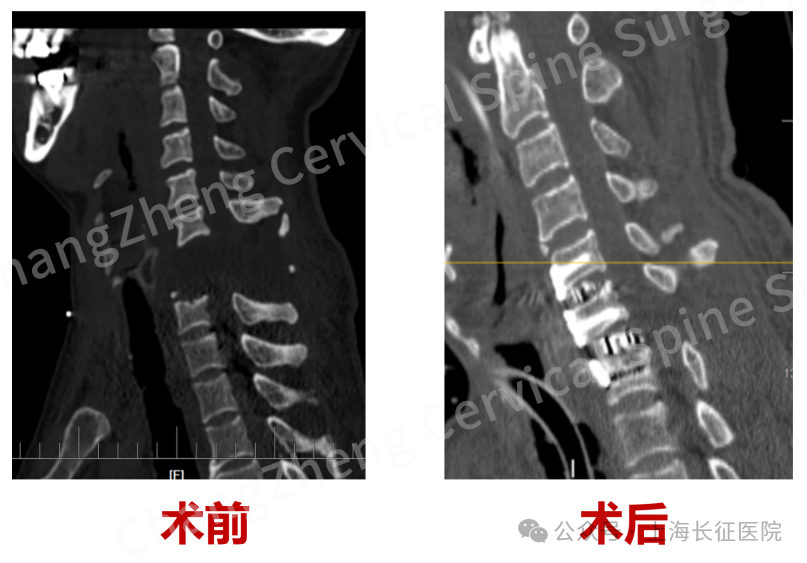

影像学检查结果更令人震惊:颈椎发生极其罕见的大跨度脱位,其严重程度犹如“身首离断”,已造成脊髓严重挫伤、关键神经血管结构撕裂。

在患者极其脆弱的生命体征监护下,专家们凭借炉火纯青的解剖功底和显微操作技术,小心翼翼地清除巨大血肿,克服严重粘连和畸形,最终精准地将完全离断错位的颈椎结构完美复位。

尤为关键的是,团队创新性地应用了“卫星钢板”固定技术,在常规固定之外巧妙增加辅助钢板,为重建的颈椎提供了前所未有的超强稳定性,这一技术应用在此类极端病例中尚属首创。

术后,患者意识状态迅速恢复清晰,一度岌岌可危的生命体征逐渐趋于平稳,成功拔除了气管插管。更令人欣喜的是,患者已能在家人辅助下坐起,标志着其神经功能开始出现积极信号,现已转入系统康复阶段,为功能恢复带来了曙光。